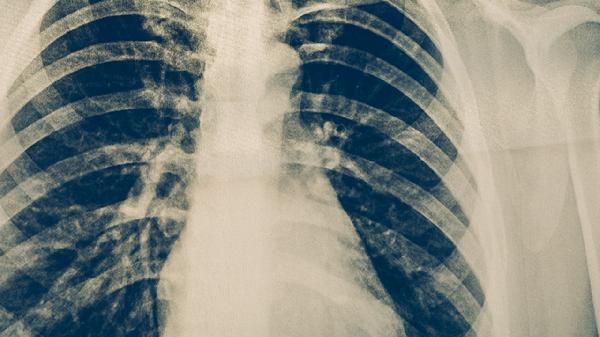

高風(fēng)險(xiǎn)人群應(yīng)每年進(jìn)行胸部X光或結(jié)核菌素試驗(yàn)篩查。長(zhǎng)期咳嗽、低熱、盜汗超過(guò)兩周者需及時(shí)就醫(yī)排查。醫(yī)務(wù)人員、監(jiān)獄工作者等職業(yè)暴露人群建議每半年檢查一次。